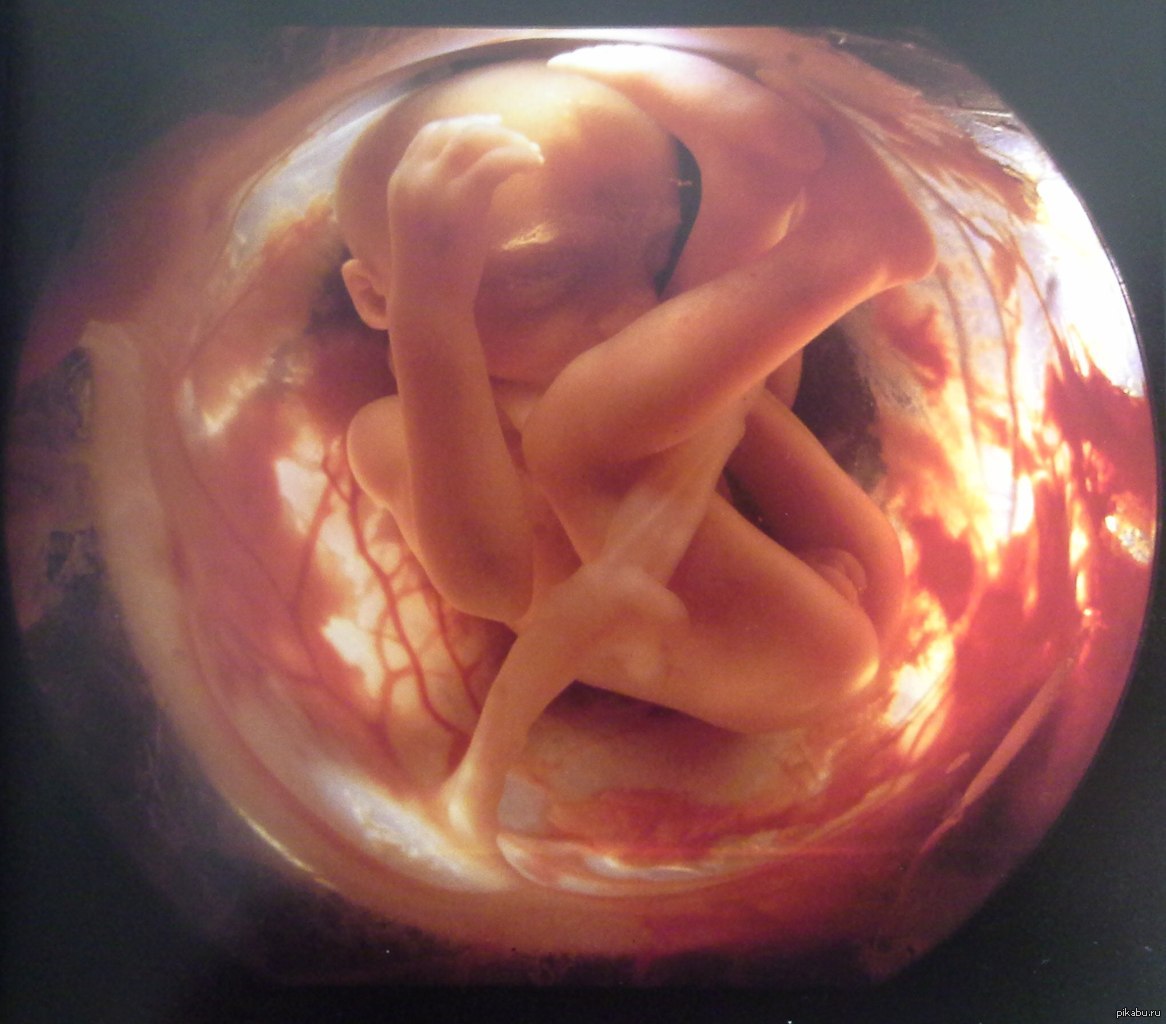

Загадочные образы животных в утробе матери